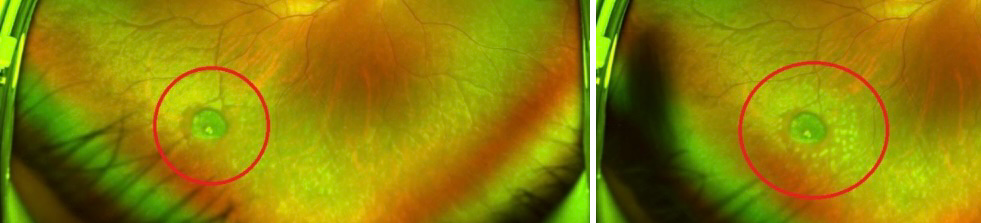

제 사진은 아니고 인터넷에서 제 안저사진의 구멍과 가장 유사한것 같은 것을 가져왔습니다.

망막에도 점이 생길수 있나요?

망막에는 다양한 이유로 점이나 변성이 생길 수 있습니다. 망막에 나타날 수 있는 점으로는 망막색소변성, 드루젠(drusen), 신생혈관, 출혈, 염증 등이 있으며 이들 각각은 다른 질환을 나타낼 수 있습니다. 망막의 점이나 변성을 평가할 때는 전문적인 안과 검사가 필요합니다. 특히 산동 검사를 통해 망막을 자세히 살펴보고, 점의 성질이나 주변 망막 조직과의 관계를 평가할 수 있습니다.

암이나 종양의 경우, 안저 사진만으로는 진단이 어렵습니다. 망막에 나타나는 암은 매우 드물지만, 망막에 종양이 생길 수는 있으며, 이를 확인하기 위해서는 추가적인 검사가 필요할 수 있습니다. 예를 들어, 초음파 검사, 형광안저혈관조영술(FA), 광학적 응집 단층 촬영(OCT) 등이 사용될 수 있습니다.